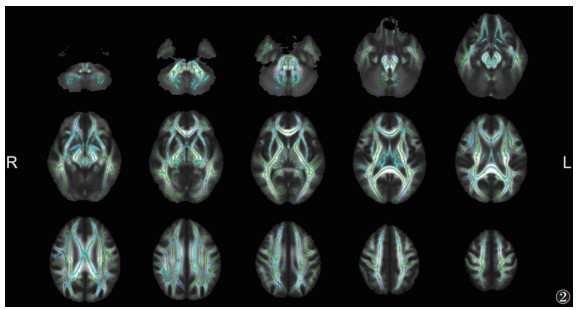

与HC组相比,ITB组脑白质的FA广泛降低、MD升高更广泛(P<0.05,TFCE和FWE校正)(图 2,3)。其中胼胝体体部、胼胝体压部、双侧前放射冠等的FA和MD同时改变(图 4)。

| 注:与HC组相比,ITB组脑白质FA降低的区域显示为蓝色(P<0.05,TFCE和FWE校正)。脑白质骨架显示为绿色。L,左;R,右 图 2 颅内结核(ITB)组与HC组各向异性分数(FA)的差异 |